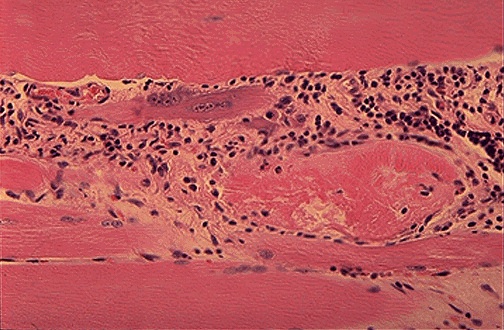

Here is another example of polymyositis. Note the degeneration of muscle fibers in the region of inflammation. Of the autoantibodies, anti-Jo1 is probably the most common with this disorder.